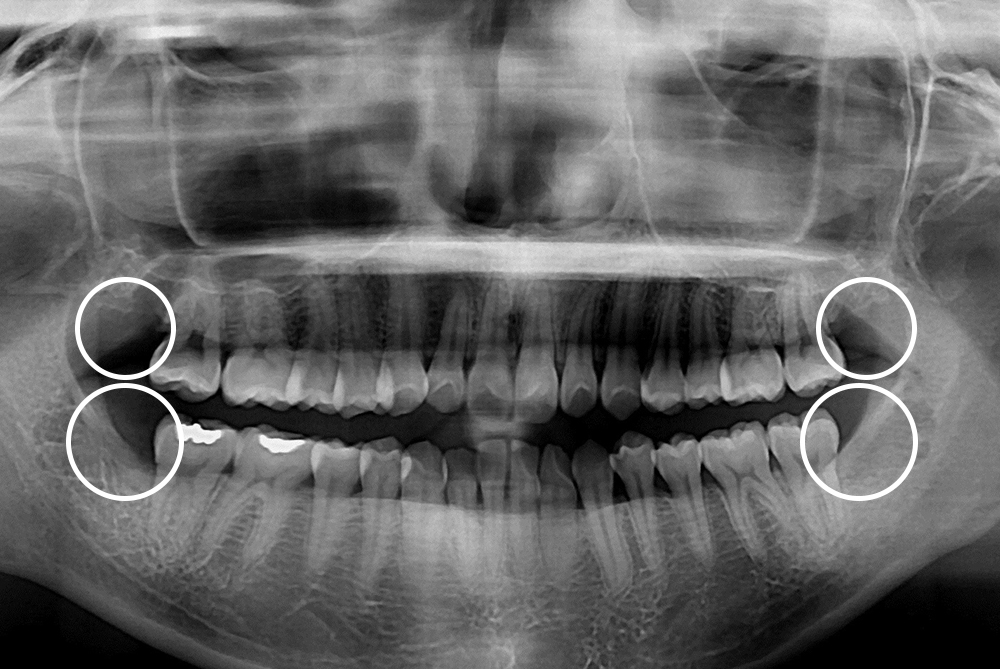

[사랑니] 매복 사랑니 발치

치료전 : 2019-01-18